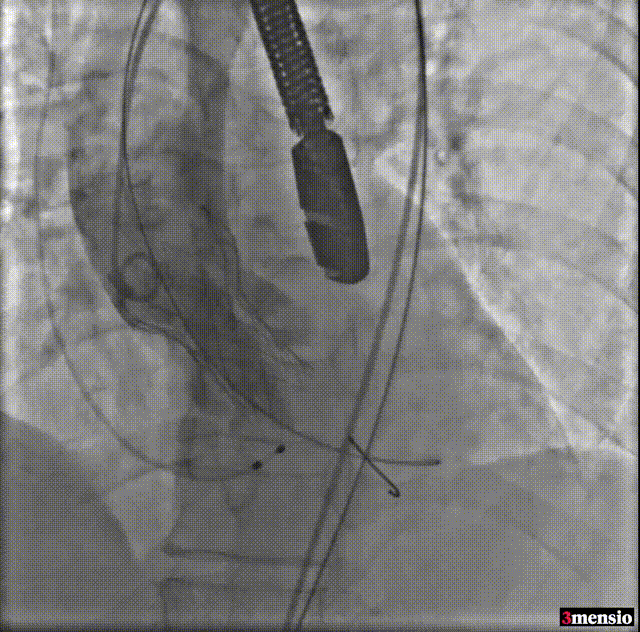

导丝跨瓣

球囊预扩

预释放定位

瓣膜释放至工作位

工作位造影

释放后造影

由于该病例瓣上限制较重,手术团队讨论决定使用沛嘉20mm球囊后扩处理:

球囊后扩

瓣膜最后形态造影